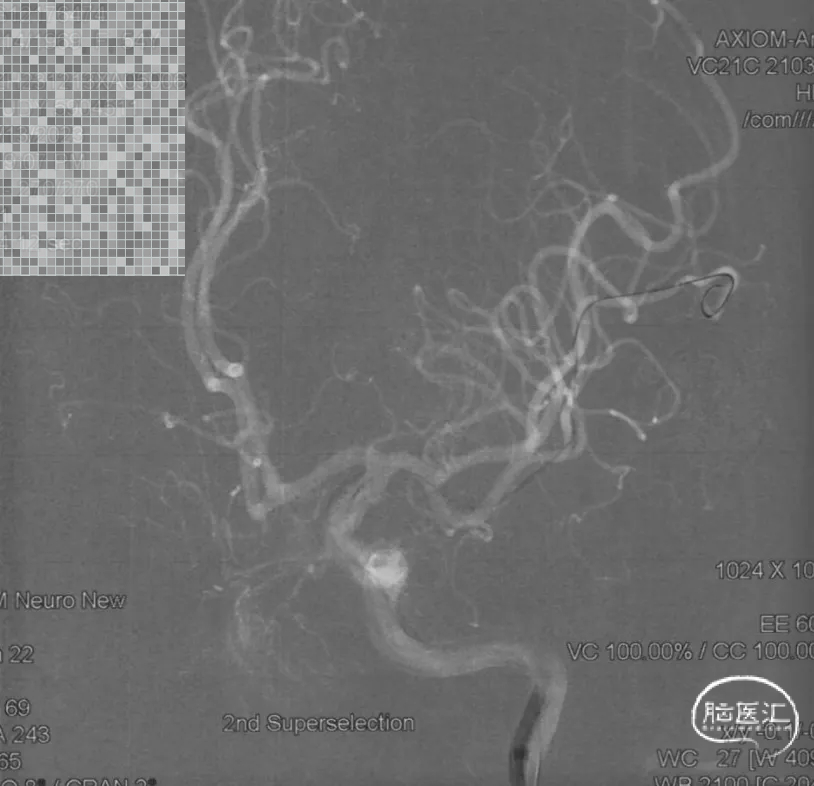

Marathon微导管在Hybrid 0.008微导丝导引下分别超选左侧大脑中供血分支、接近畸形团,采用25%的Glubran胶先后对畸形团进行了2次栓塞

第一次超选大脑中动脉分支

经Marathon造影显示导管头位置准确及畸形团和引流情况

经Marathon缓慢推注25%的Glubran,弥散效果良好,返流即快速拔管

第一支栓塞后影像

第二次超选大脑中动脉分支

经Marathon造影显示导管头位置及畸形团构筑

经Marathon缓慢推注25%的Glubran闭塞供血动脉及部分畸形团

栓塞后影像,大脑中动脉供血区域血流减少